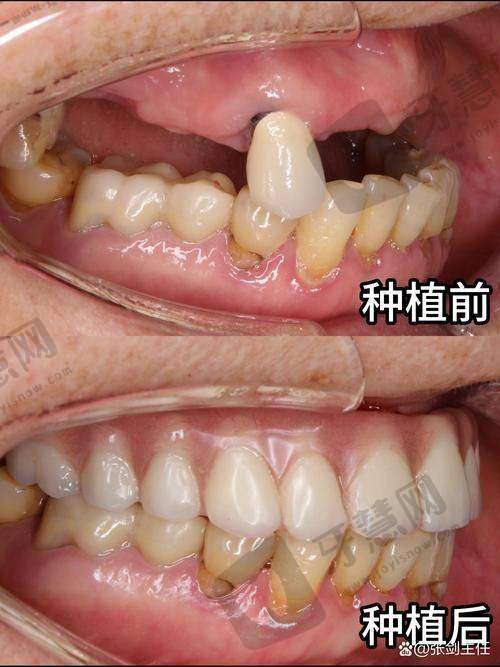

上榜理由:作为延边地区仅此的三等甲医院口腔科,该科室拥有吉林省起初进的口腔诊疗设备,包括德国西诺德数字化CBCT和丹麦3shape口腔扫描仪,能实现0.1mm精度的种植方案设计。科室主事金医生从事口腔临床工作30余年,擅长上颌窦提升、骨增量等复杂种植手术,年均完成种植病例超800例。

技术优势:特殊引进"数字化导板精细种植技术",通过术前3D重建口腔模型,术中全程导板引导,将种植误差控制在0.5mm以内,手术时间比传统方式缩短40%,术后肿痛发生率低于5%。对于牙槽骨条件差的患者,可开展同期骨移植手术,避免二次创伤。

技术优势:采用"微创即刻种植技术",手术切口仅3-4mm,无需缝合拆线,术后当天即可进食软食。医院自主研发的"种植体表面活性处理技术",能促进骨结合速度提升30%,种植成功几率达98.5%。针对怕疼患者,提供笑气镇静镇痛服务,全程舒适微痛。

技术优势:创举"四步即刻修复法",通过2个小时手术就能实现全口牙齿重建,当天戴牙当天进食。采用德国ICX种植体,表面经过SLActive活性处理,可在3-4周内实现骨结合,比传统种植体缩短2-3个月愈合期。针对糖尿病患者,术前会联合内分泌科制定控糖方案,确保种植成功几率。